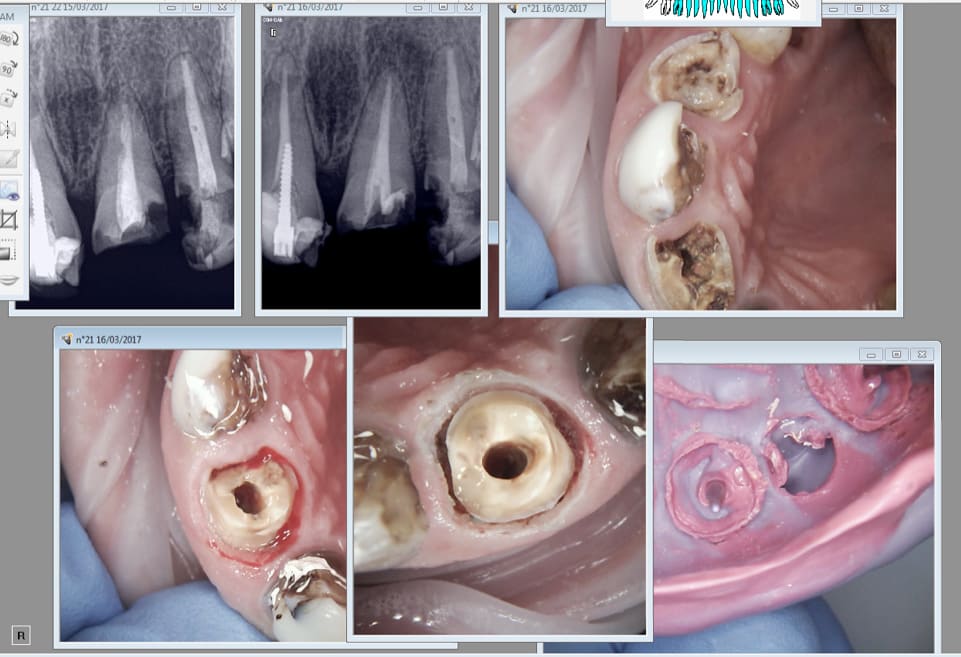

Cette 14 pas trop mal.

Capture d écran 2017 03 20 13.26 - Eugenol

ton ressenti niveau cicat ? c'est vraiment mieux qu'a la fraise ou a l’électrique ?

Oui ca saigne que dalle meme après l'essayage. Mais bon on verra dans le temps ce sont les premiers cas.